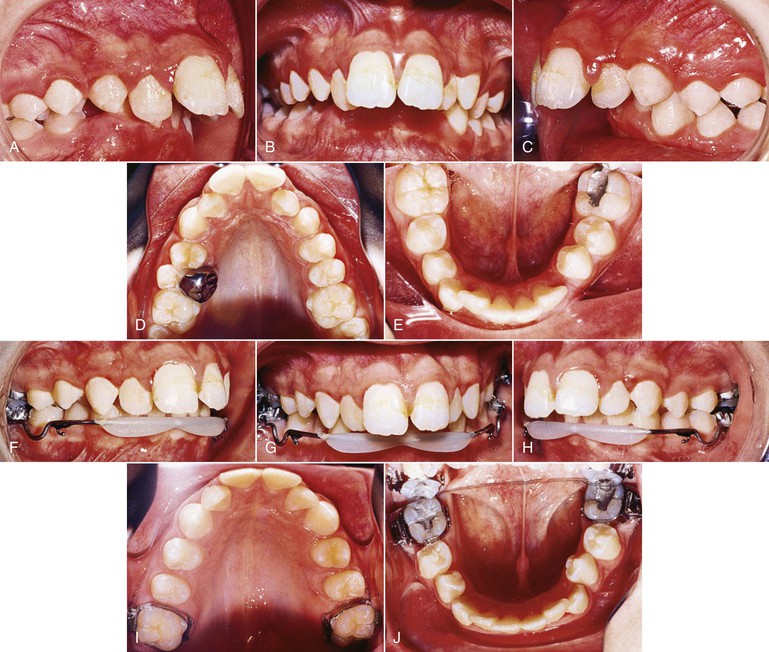

A decision to extract the second molars may be made in severe Class II cases where maximum retraction of the first molars is required. As mentioned, radiographic documentation for the presence of the third molars is important. Figure 12-1 documents a case in which extraction of the maxillary second molars was performed prior to their eruption. A mandibular lip bumper engaged to the mandibular first molar bands was used to align and unravel the minor mandibular crowding. The maxillary premolars were allowed to passively drift back. Retraction of the anterior segment, however, required active mechanics and this was accomplished using a T-loop. Class II elastics were used for 1 month. During this process the headgear was used as anchorage and the patient wore it only at bedtime.

Figure 12-1 Headgear treatment. A–E, Pre-treatment intraoral photographs. A stainless steel crown is present on the exfoliating maxillary left second primary molar. F–J, Progress photographs show the lip bumper in place. K–O, Intraoral photographs 1 month post-treatment. Total treatment time was 23 months.